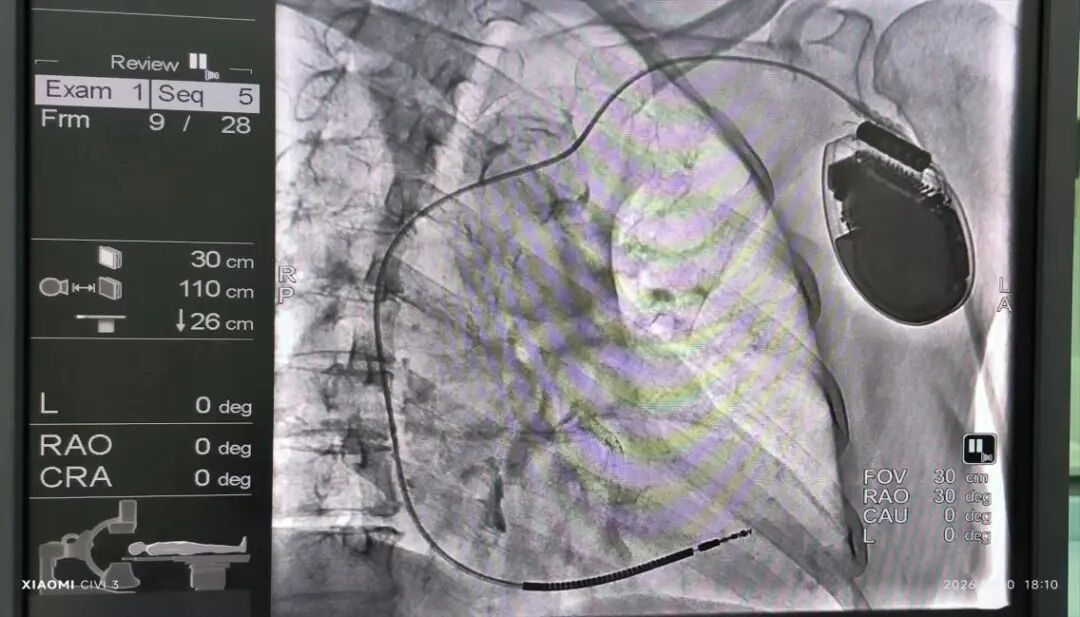

近日,济南市第五人民医院心内二科电生理团队在李贵才主任的带领下,由邱乃艳副主任医师、刘军主治医生为患者成功植入院内首例3T核磁兼容植入式心脏复律除颤器(ICD),为挽救一名罹患恶性心律失常患者生命保驾护航。

接受此次手术的患者孙女士(化名)称近期曾突发晕厥伴意识丧失,到济南市第五人民医院急诊治疗抢救成功后转入心内二科。动态心电图显示孙女士尖端扭转型室性心动过速,经心内二科电生理团队评估后,决定为她植入心脏复律除颤器(ICD)。整个手术过程顺利,耗时约1.5小时,患者无明显疼痛感觉,术后送至普通病房观察。